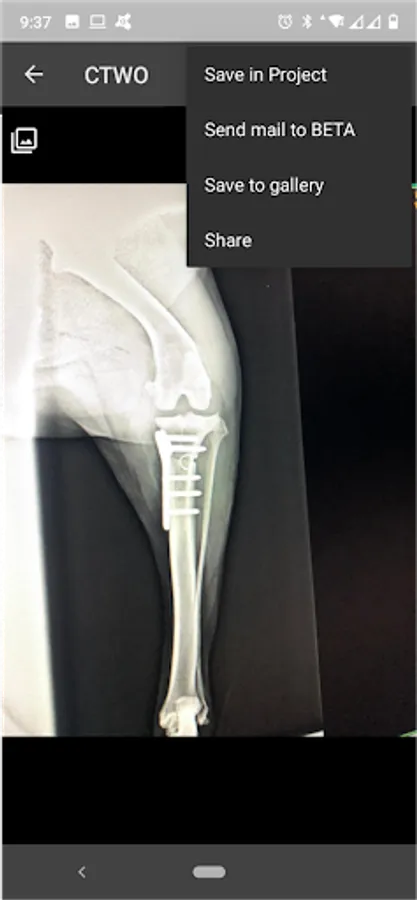

5. Share your results

6. Save in project